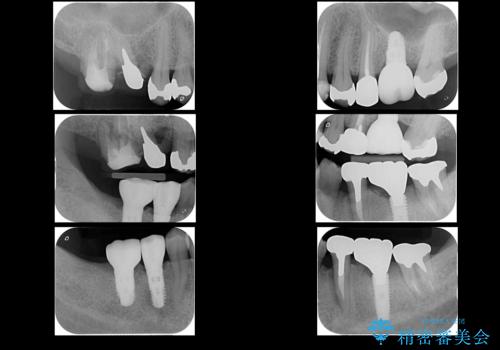

- 他院で奥歯が割れている為抜歯が必要と言われたとのことで来院。

右上56および左下5は割れていたためやむなく抜歯しインプラントにしていきました。

左下7(一番奥の歯)は抜歯をせずに済みましたが、高さがないため上の歯を矯正治療で沈め、また、歯ぐきの手術を合わせて行いクラウン(被せ物)をしっかり入れる処置をおこなっています。